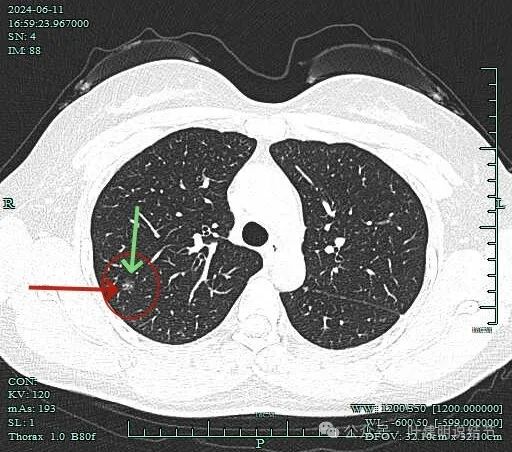

表面不平,有小血管进入病灶,病灶内部有点状偏高密度,整体轮廓清楚。

血管有异常增粗的表现,病灶表面有毛刺,灶内实性成分明显,此层磨玻璃成分占比少。